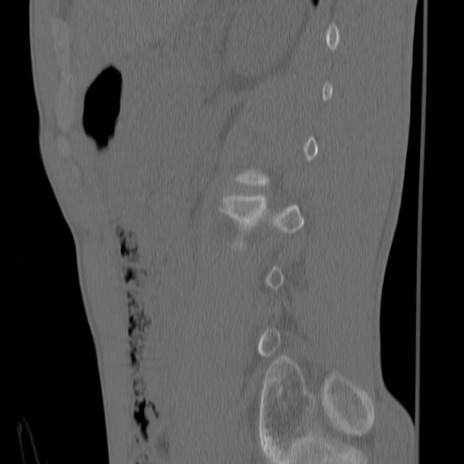

症例3 腰椎CT(矢状断像)

【症例】30歳代男性

【主訴】腰痛

【現病歴】本日旅行先で観光中に、友人と衝突し転倒し受傷。

【身体所見】麻痺なし、右下腿内側前面外側、左下腿内側に知覚鈍麻・しびれ

異常所見と診断は?

腰椎CT

冠状断像